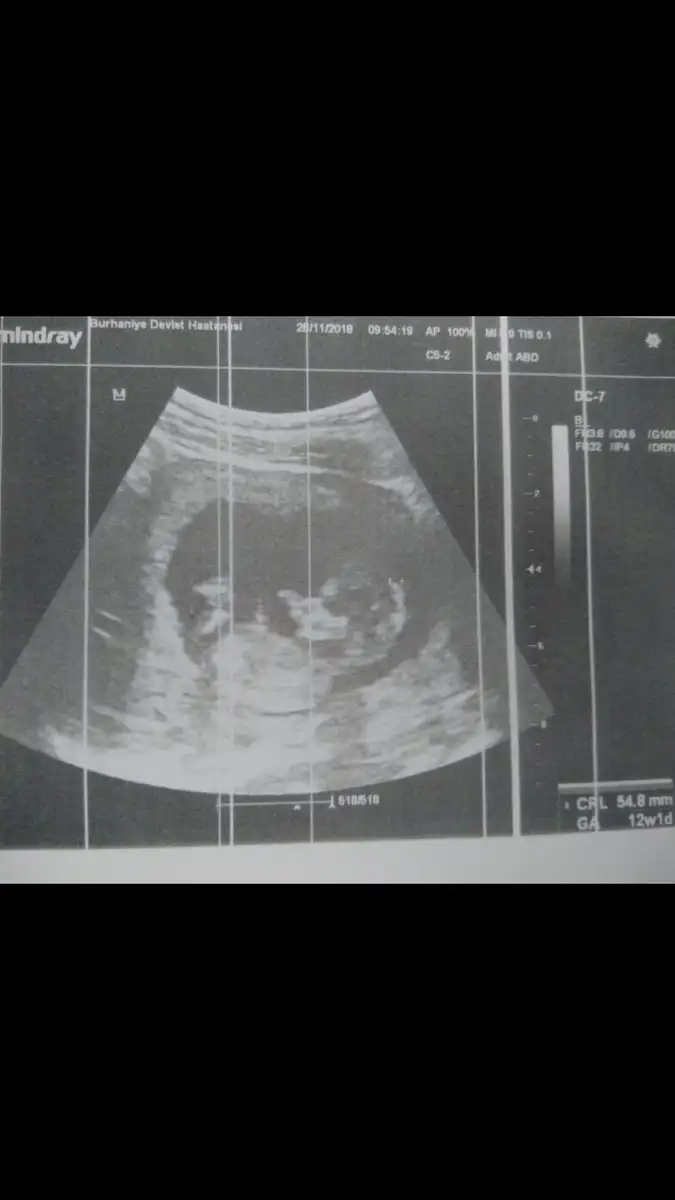

Biz geldik kızlar bebiş gayet sağlıklı her şeyi iyi ilk defa kalp atışını dinledik sonunda çok şükür ikili test yatırmadım ama ense kalınlığı iyi dedi zaten %99 down sendromlu değil bebek dedi cinsiyeti ben gördüm çıkıntıyı ama doktor söylemedi erken diye sonra bidaha sordum çıkıntı var diye kızdı bu sefer önceliğin cinsiyet olmasın diye halbuki ben gördüm diye söyledim yani.. Çıkıntı yukarı bakıyordu ama doktorda çıkıntı var ama bidahakine söylerim yanılma payı var dedi onun dışında gece kahverengi leke gelmişti kese arkasında kanama var hafif dedi yat dinlen bol bol ilişki falan yasak dedi gripten çok öksürüyordum o zorlamış olabilir dedi öksürük için enfeksiyon hastalıklarına yolladı tahlil falan verdim gene bakalım kızlar bidaha leke gelirse gel dedi devamı gelmez inşallah :/ 1 hafta 2 günde gerideyiz gene Screenshot_20181128-131317.webp

Biz geldik kızlar bebiş gayet sağlıklı her şeyi iyi ilk defa kalp atışını dinledik sonunda çok şükür ikili test yatırmadım ama ense kalınlığı iyi dedi zaten %99 down sendromlu değil bebek dedi cinsiyeti ben gördüm çıkıntıyı ama doktor söylemedi erken diye sonra bidaha sordum çıkıntı var diye kızdı bu sefer önceliğin cinsiyet olmasın diye halbuki ben gördüm diye söyledim yani.. Çıkıntı yukarı bakıyordu ama doktorda çıkıntı var ama bidahakine söylerim yanılma payı var dedi onun dışında gece kahverengi leke gelmişti kese arkasında kanama var hafif dedi yat dinlen bol bol ilişki falan yasak dedi gripten çok öksürüyordum o zorlamış olabilir dedi öksürük için enfeksiyon hastalıklarına yolladı tahlil falan verdim gene bakalım kızlar bidaha leke gelirse gel dedi devamı gelmez inşallah :/ 1 hafta 2 günde gerideyiz gene Eki Görüntüle 2210124